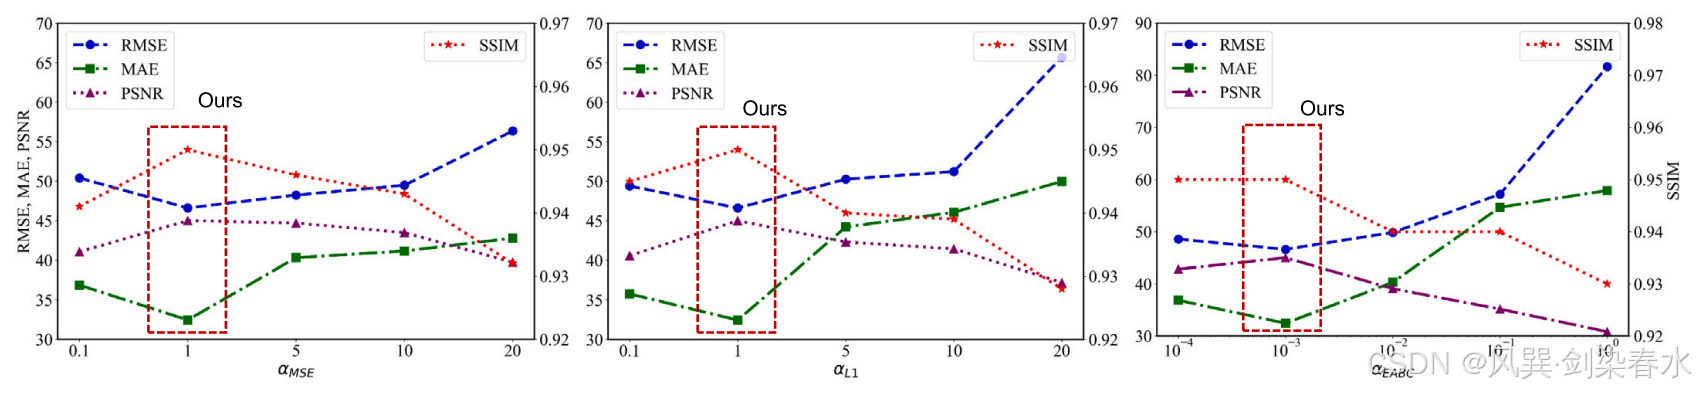

在这里, α α α 表示每个损失的系数,反映了该损失在总体损失计算中的相对重要性。在本研究中,设定了 α E A B C = 10 − 3 α_{EABC}=10^{−3} αEABC=10−3, α M S E = α L 1 = 1 α_{MSE}=α_{L_1}=1 αMSE=αL1=1 。

Figure 6 | 网络训练过程中对验证数据集的评估结果: